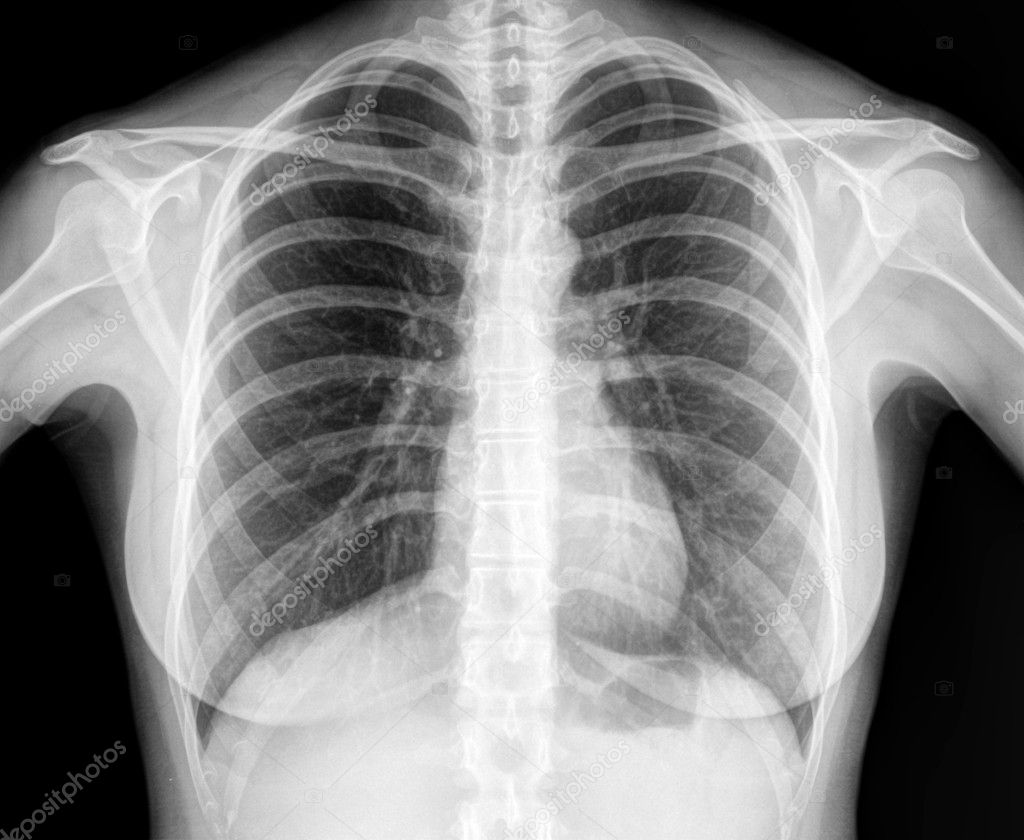

chest x ray Ray chest human healthy stock depositphotos

stock.adobe.comX-Ray Image Of Human Healthy Chest — Stock Photo © Jovannig #11802437

stock.adobe.comX-Ray Image Of Human Healthy Chest — Stock Photo © Jovannig #11802437

depositphotos.comray chest human healthy stock depositphotos

depositphotos.comray chest human healthy stock depositphotos